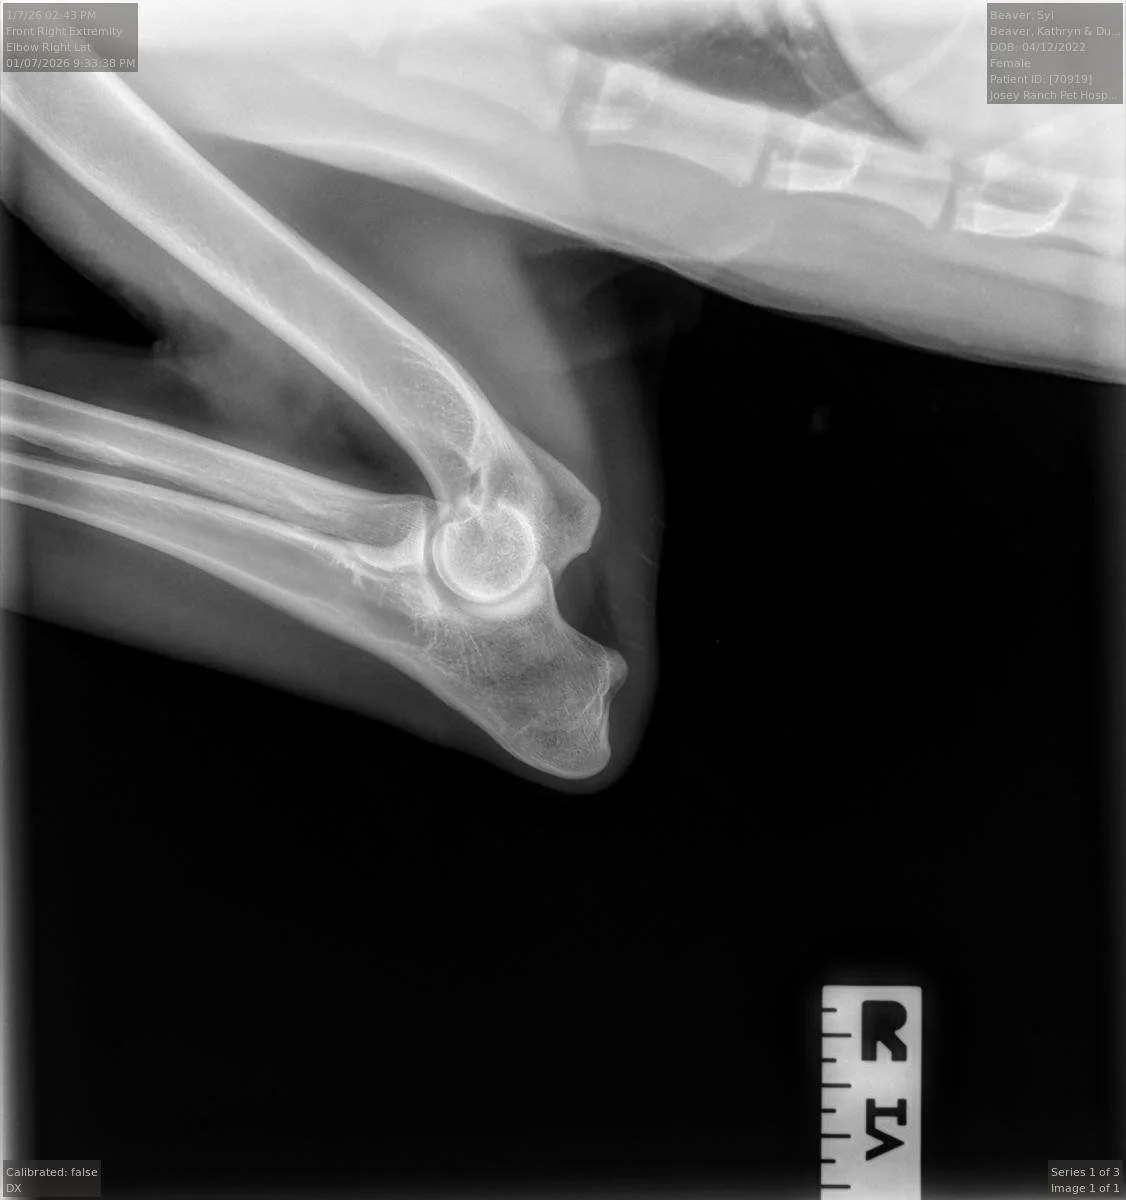

Syl’s right elbow x-ray, taken at 2 years and 9 months old, intact.